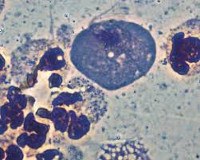

Микоплазма (Mycoplasma hominis) относится к группе урогенитальных микоплазм. Микоплазмы являются условно-патогенными микроорганизмами и часто встречаются у здоровых людей. Его патогенность зависит от определенных условий, концентрации, наличия в организме другой патогенной флоры (трикомонады, хламидии, гонококки и ).

Преимущественное заражение микоплазмой происходит половым путем, также возможна вертикальная инфекция плода во время беременности или инфекция во время родов. Микоплазмы - это внутриклеточные паразиты, которые населяют клеточные мембраны хозяина, вызывая нарушение клеточных функций и местные воспалительные реакции. Микоплазмоз характеризуется латентным течением с обострениями, хроническим течением или рецидивом процесса под влиянием нескольких факторов.